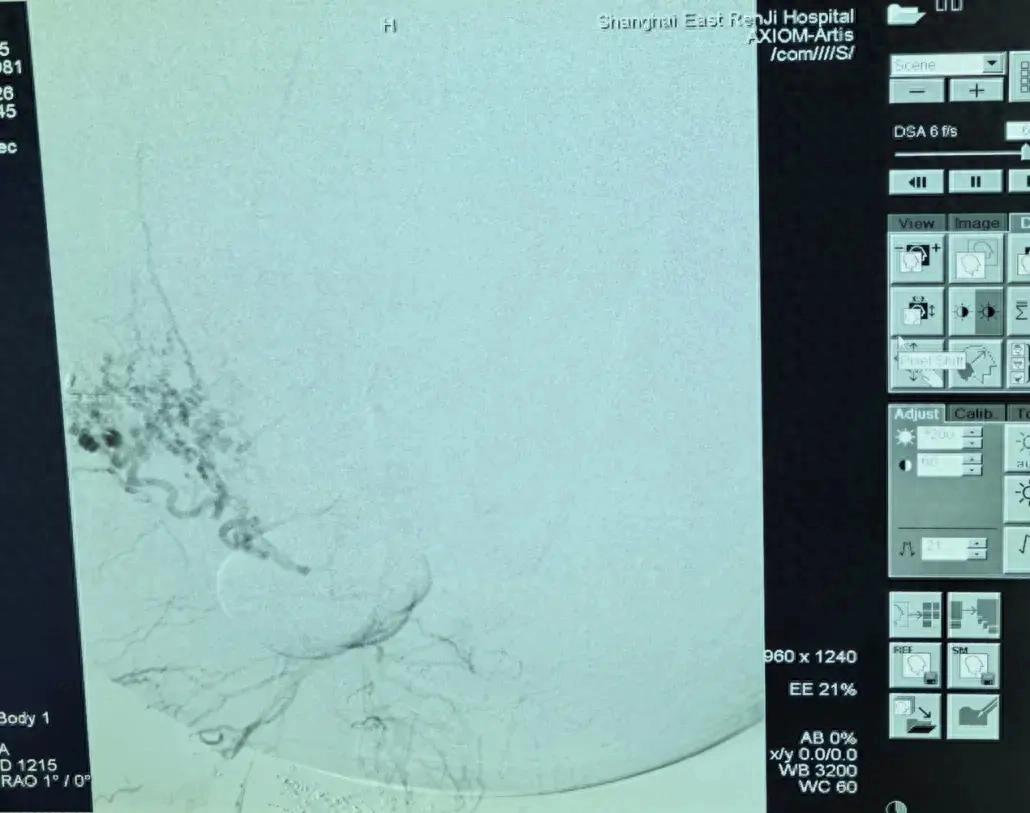

第一棒交给肿瘤介入科主任张学彬。在DSA(数字减影血管造影)的精准引导下,张学彬凭借娴熟的技术,成功找到并栓塞了肿瘤的多支滋养动脉,为后续手术清除了最大的“路障”。